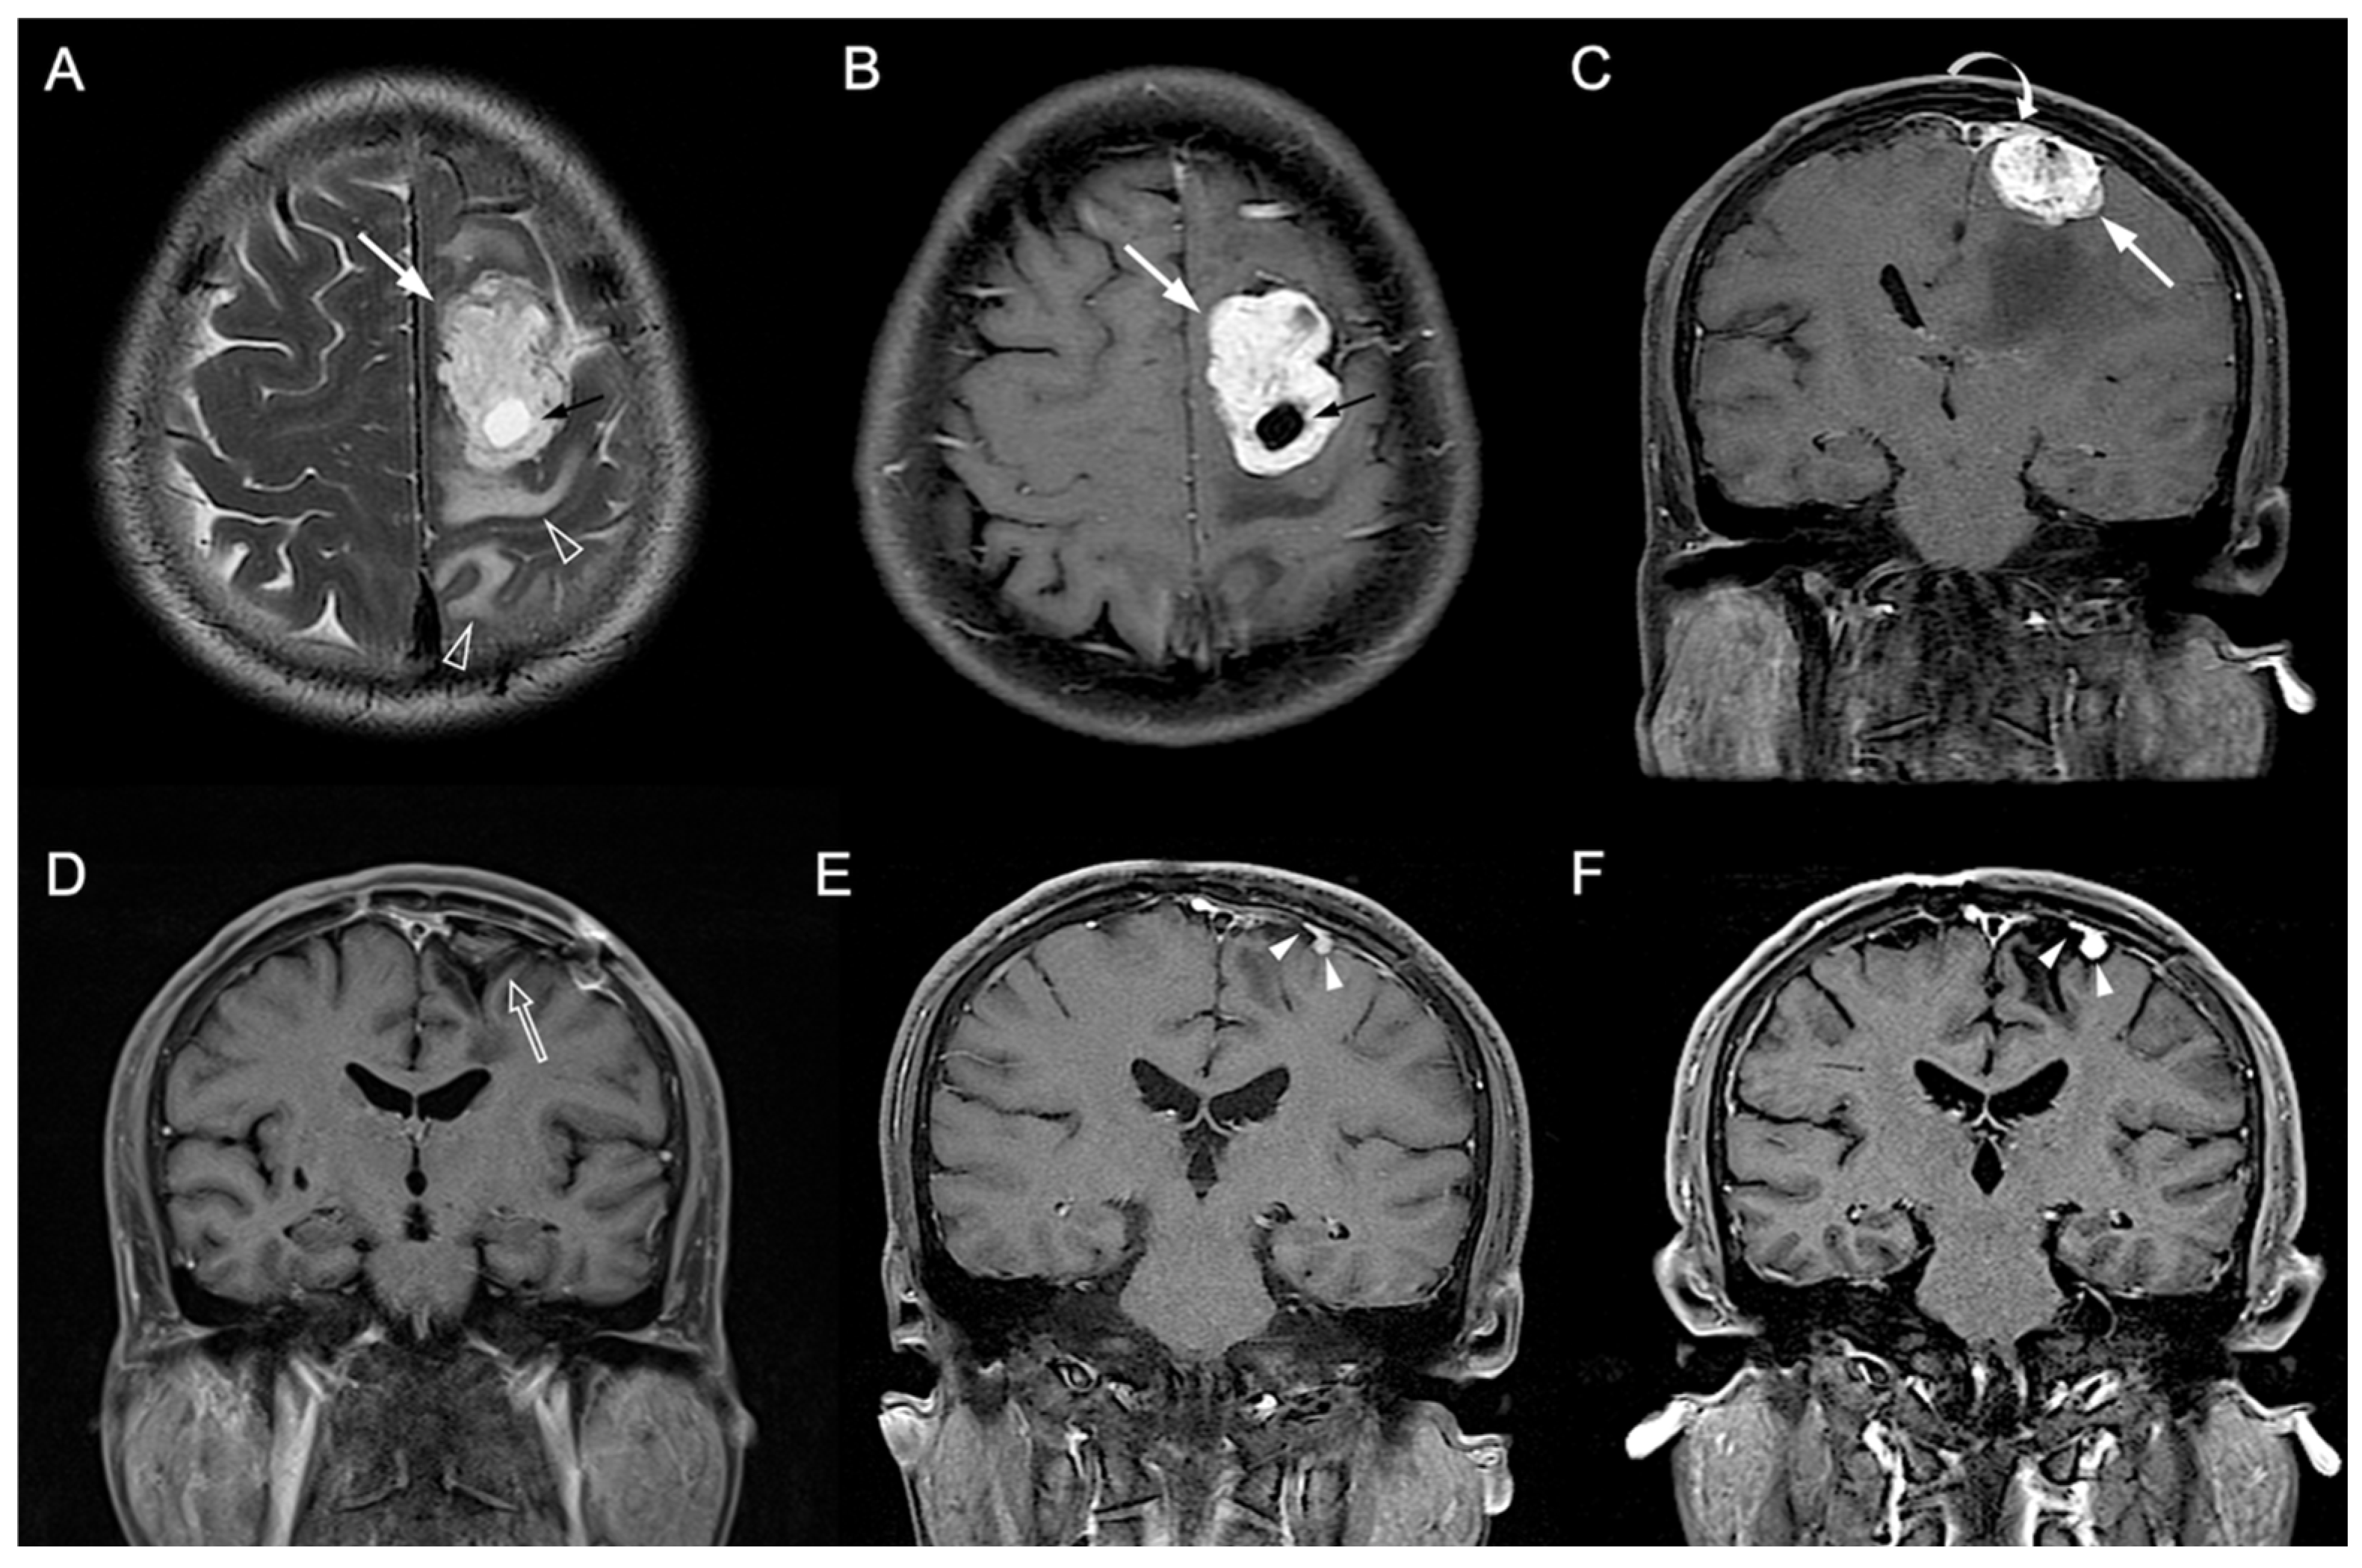

Figure 3.

A 54-year-old man with pathologically proven parasagittal meningioma (WHO grade I). (A) Axial T2WI and (B) CE T1WI shows a left parasagittal enhancing tumor mass (white arrow) with peritumoral edema (open arrowhead) and intratumoral cystic change (black arrow). (C) Coronal CE T1WI shows the left parasagittal enhancing mass (white arrow) with invasion of left lateral recess (white curved arrow) of the superior sagittal sinus. The preoperative radiomic score based on the selected clinical and texture features is 0.503. (D) Gross total resection is performed, and no residual tumor (open arrow) was detected after surgery. (E,F) Progressive recurrence of tumor (white arrowheads) was observed in 27 months (E) and 47 months (F) after surgery.